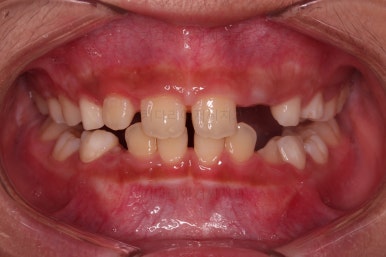

마찬가지로 초진시의 입안 모습입니다.

보호자분 말씀처럼 윗니가 아랫니에 비해서 나와보이는게 사실이네요.

그럼 정말 윗니가 튀어나온게 맞을까요?

이번 환자분은 무턱 + 돌출입 성장교정이 목표였지만 그전에 치아의 맹출경로가 엉켜서(화살표) 치아의 손상 혹은 매복치아의 우려가 있는 부분을 먼저 개선하기로 했습니다.

위치가 나빴던 앞니가 제위치로 갔고, 위아래 앞니도 서로 가까워졌어요.

앵글씨 2급 부정교합이 개선된거죠.

아래턱-위턱이 차이날 때 필연적으로 생기는 과개교합(앞니가 서로 깊게 맞물리는 교합)도 개선되었고요.